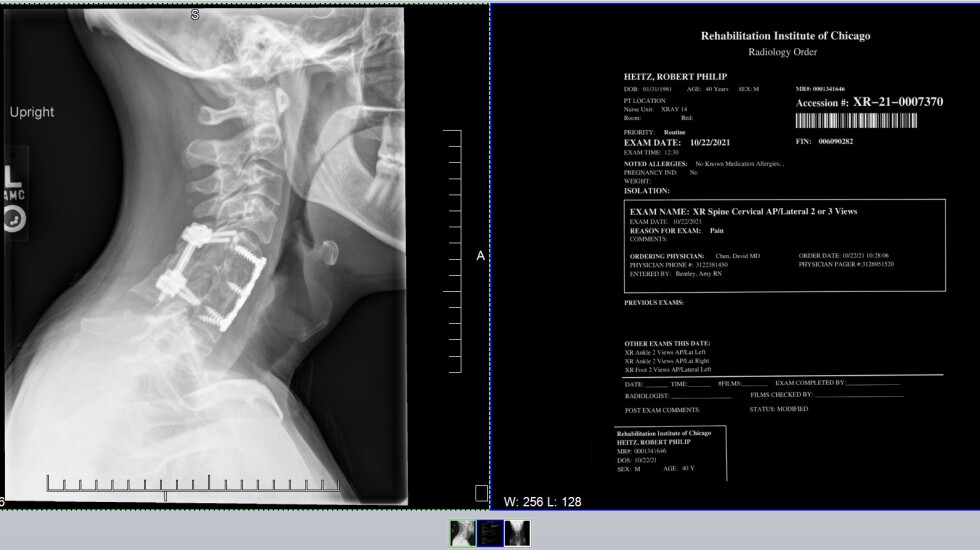

Heitz’s father, then a personal injury attorney, quickly found a specialist at Northwestern Memorial Hospital. The impact from the dive had shattered one of the vertebrae in Heitz’s neck. The spinal cord had been damaged but not severed. Surgeons fashioned a vertebra from a piece of Heitz’s hipbone and fused two other vertebrae together. Titanium plates and screws hold it all together.

He was transferred to the Rehabilitation Institute of Chicago, now the Shirley Ryan AbilityLab. There, he was offered a chance to participate in a study using a robotic device that would eventually retrain his brain and body to walk again.